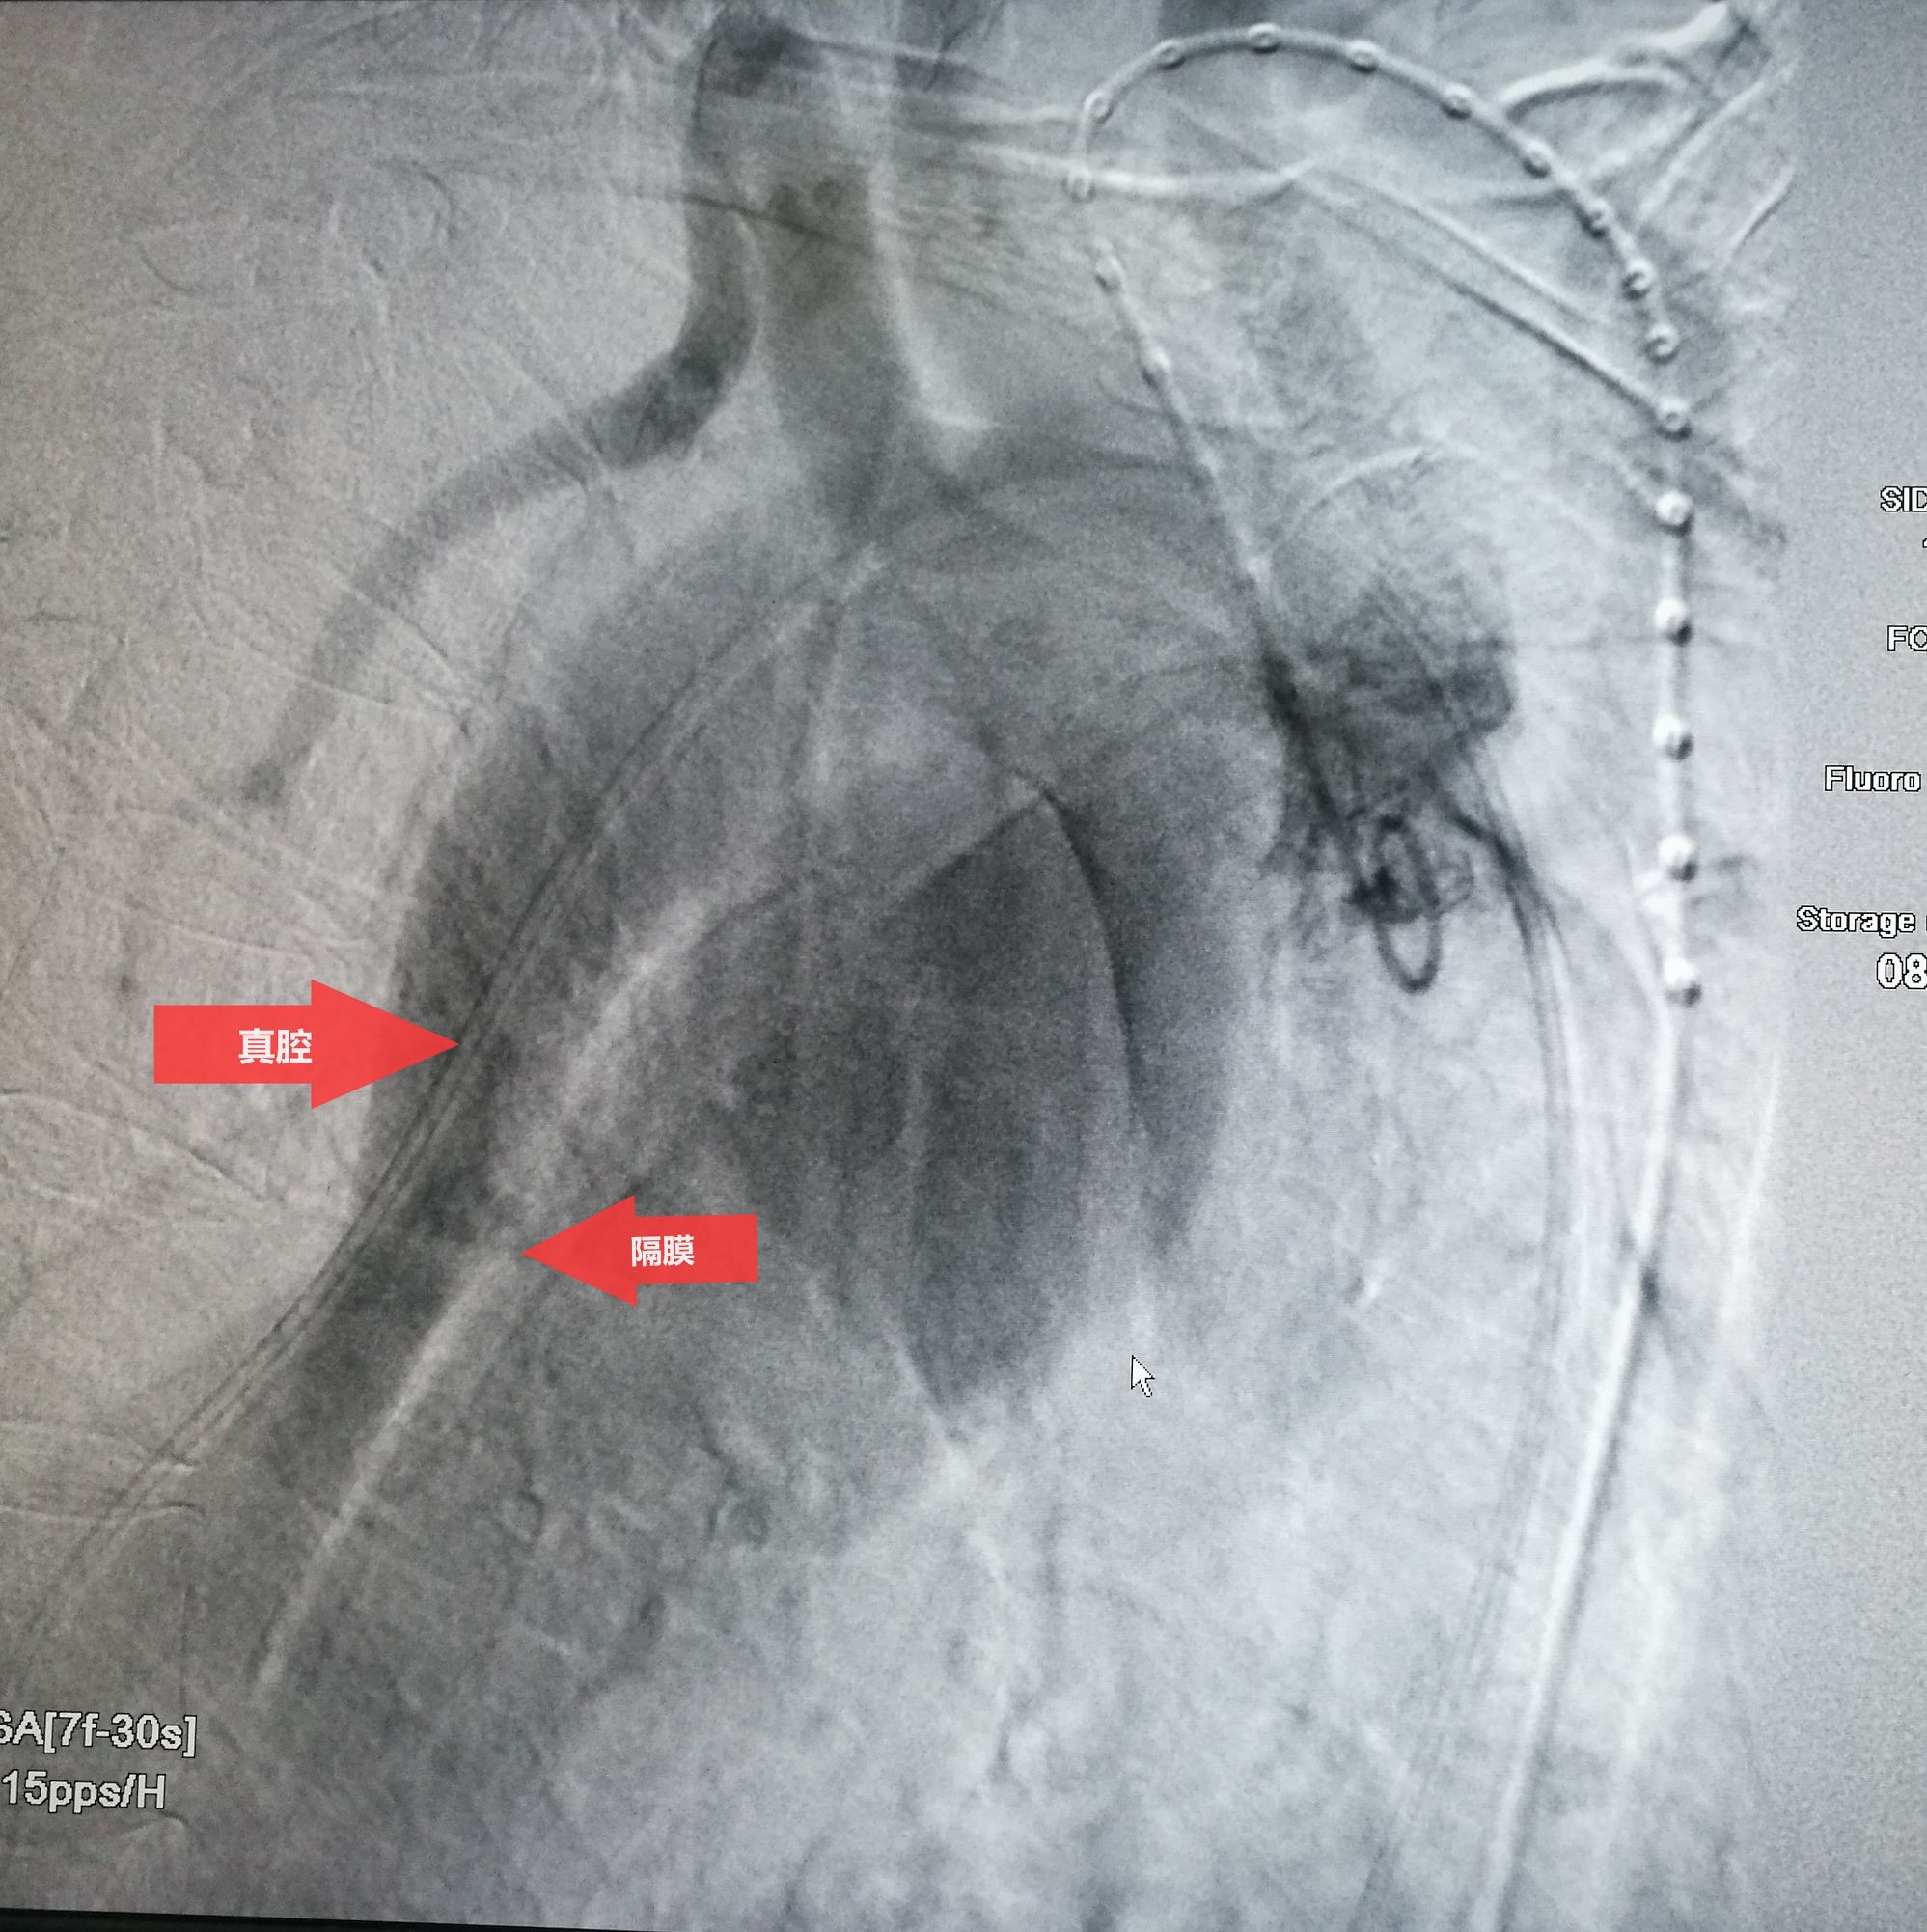

此例患者进行发病时未能确诊,进入慢性期后假腔扩张瘤样变。在CT的部分层面,食道受压看不到。重建影像可见假腔扩张,动脉扭曲。

手术在局麻下进行,经右股动脉穿刺置管到升主,经左桡动脉穿刺植入金标猪尾导管,造影,为确认真假腔,加做右前斜位造影,确认股动脉导管在真腔内,测量后植入覆膜支架。由于扭曲严重(腹主,膈肌附近,弓降),支架最初并未贴服大湾侧,支架送过锁骨下动脉后适当回撤,请拉释放导丝,此时支架整体向大弯侧轻微移动,考虑应力已经得到缓解。完全释放支架,定位良好,封堵完全无内漏。